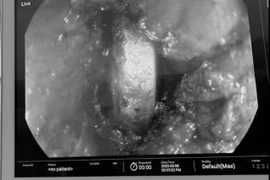

Bệnh viện Sản nhi Phú Thọ vừa nội soi khẩn, gắp thành công pin cúc áo mắc trong thực quản bé 2 tuổi, tránh nguy cơ bỏng loét, thủng thực quản đe dọa tính mạng.